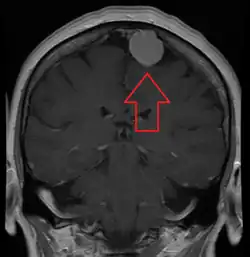

![]() | |

| An MRI of the brain, demonstrating the appearance of a meningioma | |